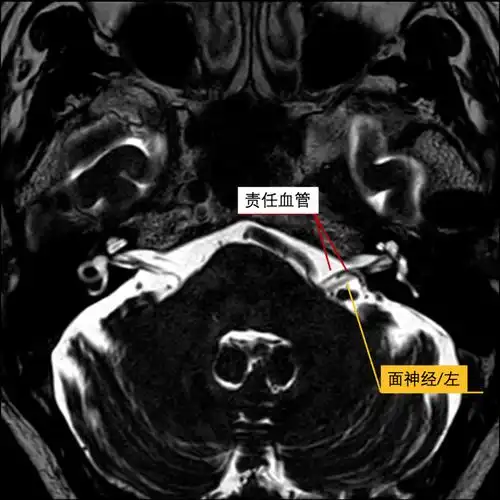

三叉神经痛,面肌痉挛手术前的主要影像学检查

三叉神经(痛),面神经面肌痉挛血管磁共振成像mrta技术 - 好大夫在线